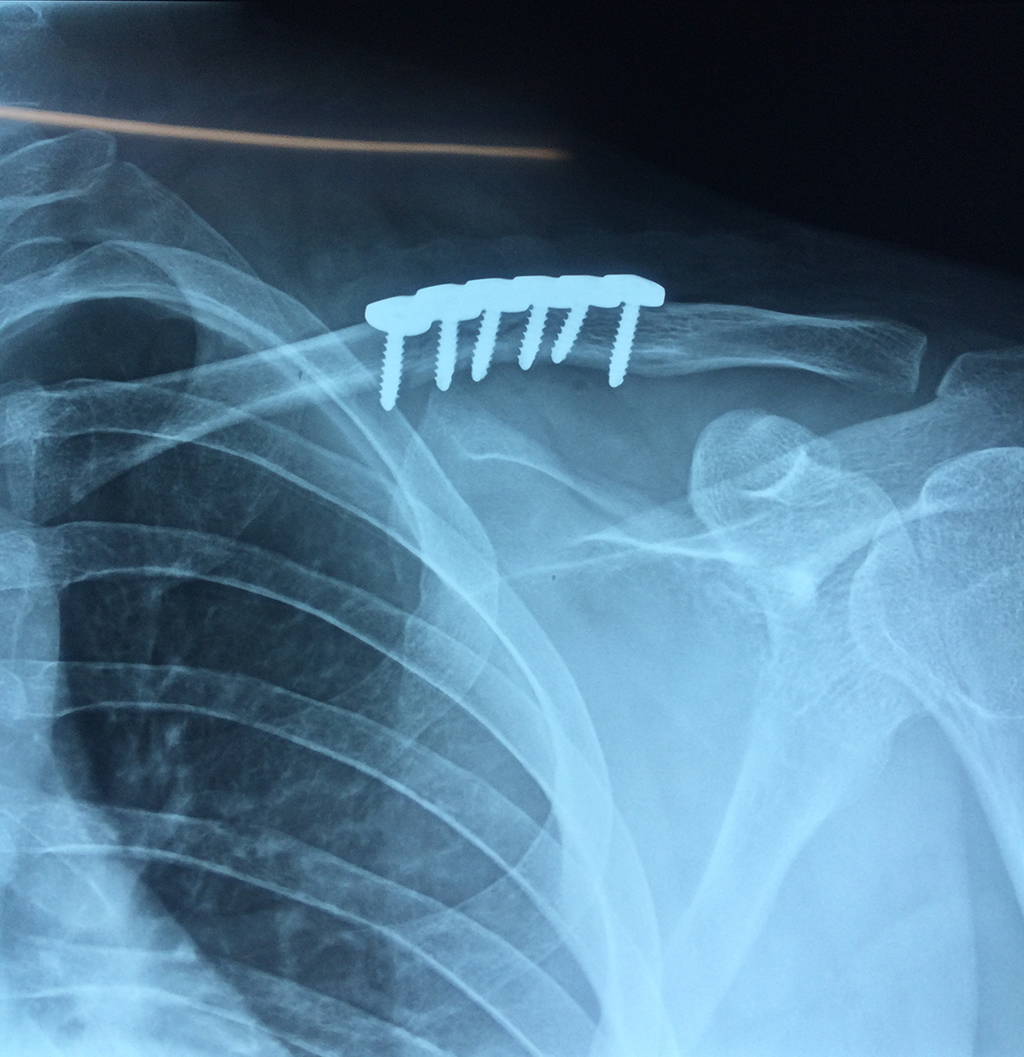

Cirugías de Hombros - Clavícula

La clavícula es un hueso largo, con forma de "S" itálica, situado en la parte anterosuperior del tórax. Junto con la escápula forman la cintura escapular. Se puede palpar por toda su longitud y se extiende del esternón al acromion de la escápula, siguiendo una dirección oblicua lateral y posterior.

Se considera el único medio de unión entre el miembro superior y el tórax. A pesar de su aspecto, similar al de un hueso largo, posee una estructura semejante a la de un hueso plano, ya que carece de epífisis y de diáfisis, lo que la harían entrar dentro de la clasificación de hueso largo. Carece de un canal medular propiamente dicho.